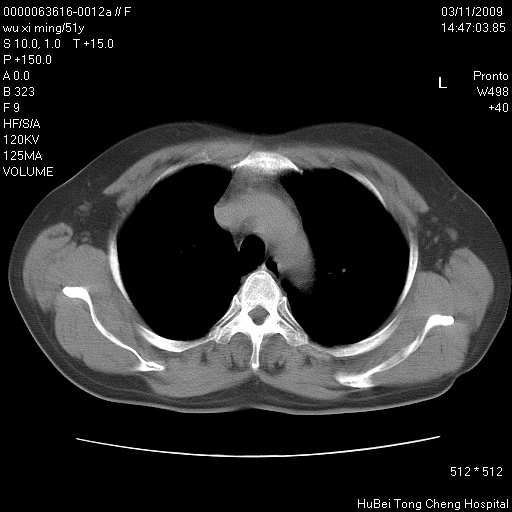

患者 女,51岁。因“胆囊炎,胆囊结石”,行常规术前胸部x线检查发现:右上肺结节病灶,建议行进一步检查。患者无咳嗽、咳痰及咯血等呼吸道症状,近期出现背部疼痛不适。

胸部ct轴位平扫(层厚10mm,螺距1.5,重建间隔10mm;部分层面:层厚3mm,螺距1.0,重建间隔3mm),图像如下:

右肺周围型肺癌伴肺内转移信胸椎转移

支持--右肺周围型肺癌---胸椎转移

右肺周围型肺癌伴肺内转移及胸椎转移。已无手术机会。